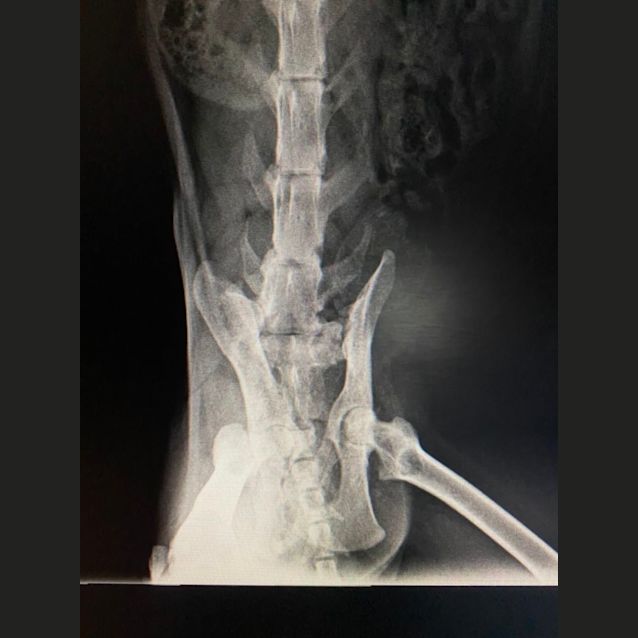

Jolene has a severe limp, stemming from the pelvis/hip, the leg is non weight bearing. Her veterinarian assures us she is not in any pain and I have never observed any indication of discomfort either.

Our veterinarian will be more that happy to discuss her condition with you, I’ve also added photos of her radiographs to the gallery.